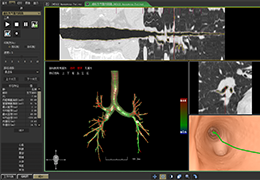

Volume Rendering

Volume rendering is performed with a very fast ray casting algorithm; lightning calculations are based on Phong-shading. Surface rendering of reconstructed surfaces is performed using OpenGL. Using texture mapping, a reconstructed surface (e.g., head or brain) may be sliced in real time, showing both surface and volume data at the same time. Initial polygon meshes serve as the basis for surface finding, cortex inflation and cortex flattening computations.